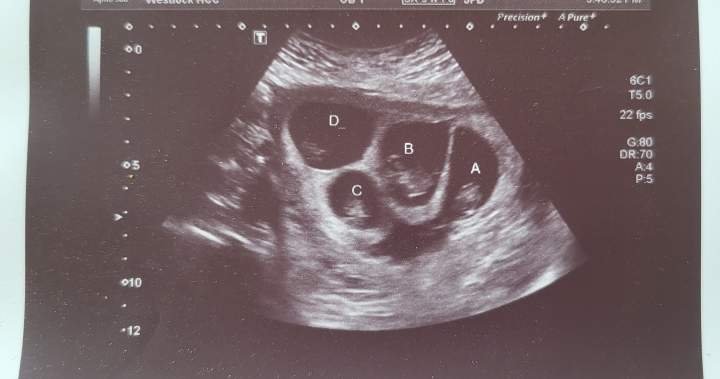

Alberta mother prepares to welcome ‘miracle’ quadruplets

She’s now six months pregnant with quadruplets: three boys and one girl. When she found out, she was in shock.